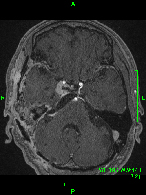

症例1) 65歳男性、頭蓋底部巨大髄膜腫、外科手術のみ

<画像所見>

巨大脳腫瘍を認める。

錐体斜台部巨大髄膜腫を認め、

神経や血管を巻き込んでいる。